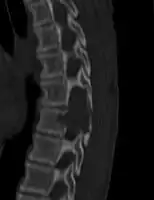

X-ray and CT scan show lytic expansion lesions with clear borders.[1] Expansion of cortex gives the lesion a balloon-like appearance. Larger lesions may appear septated.[10] MRI reveals fluid levels.[1] Bone scan shows outer radiotracer uptake, with a central dark area.[1]

CT scan: ABC fibula -

CT scan: ABC spine -